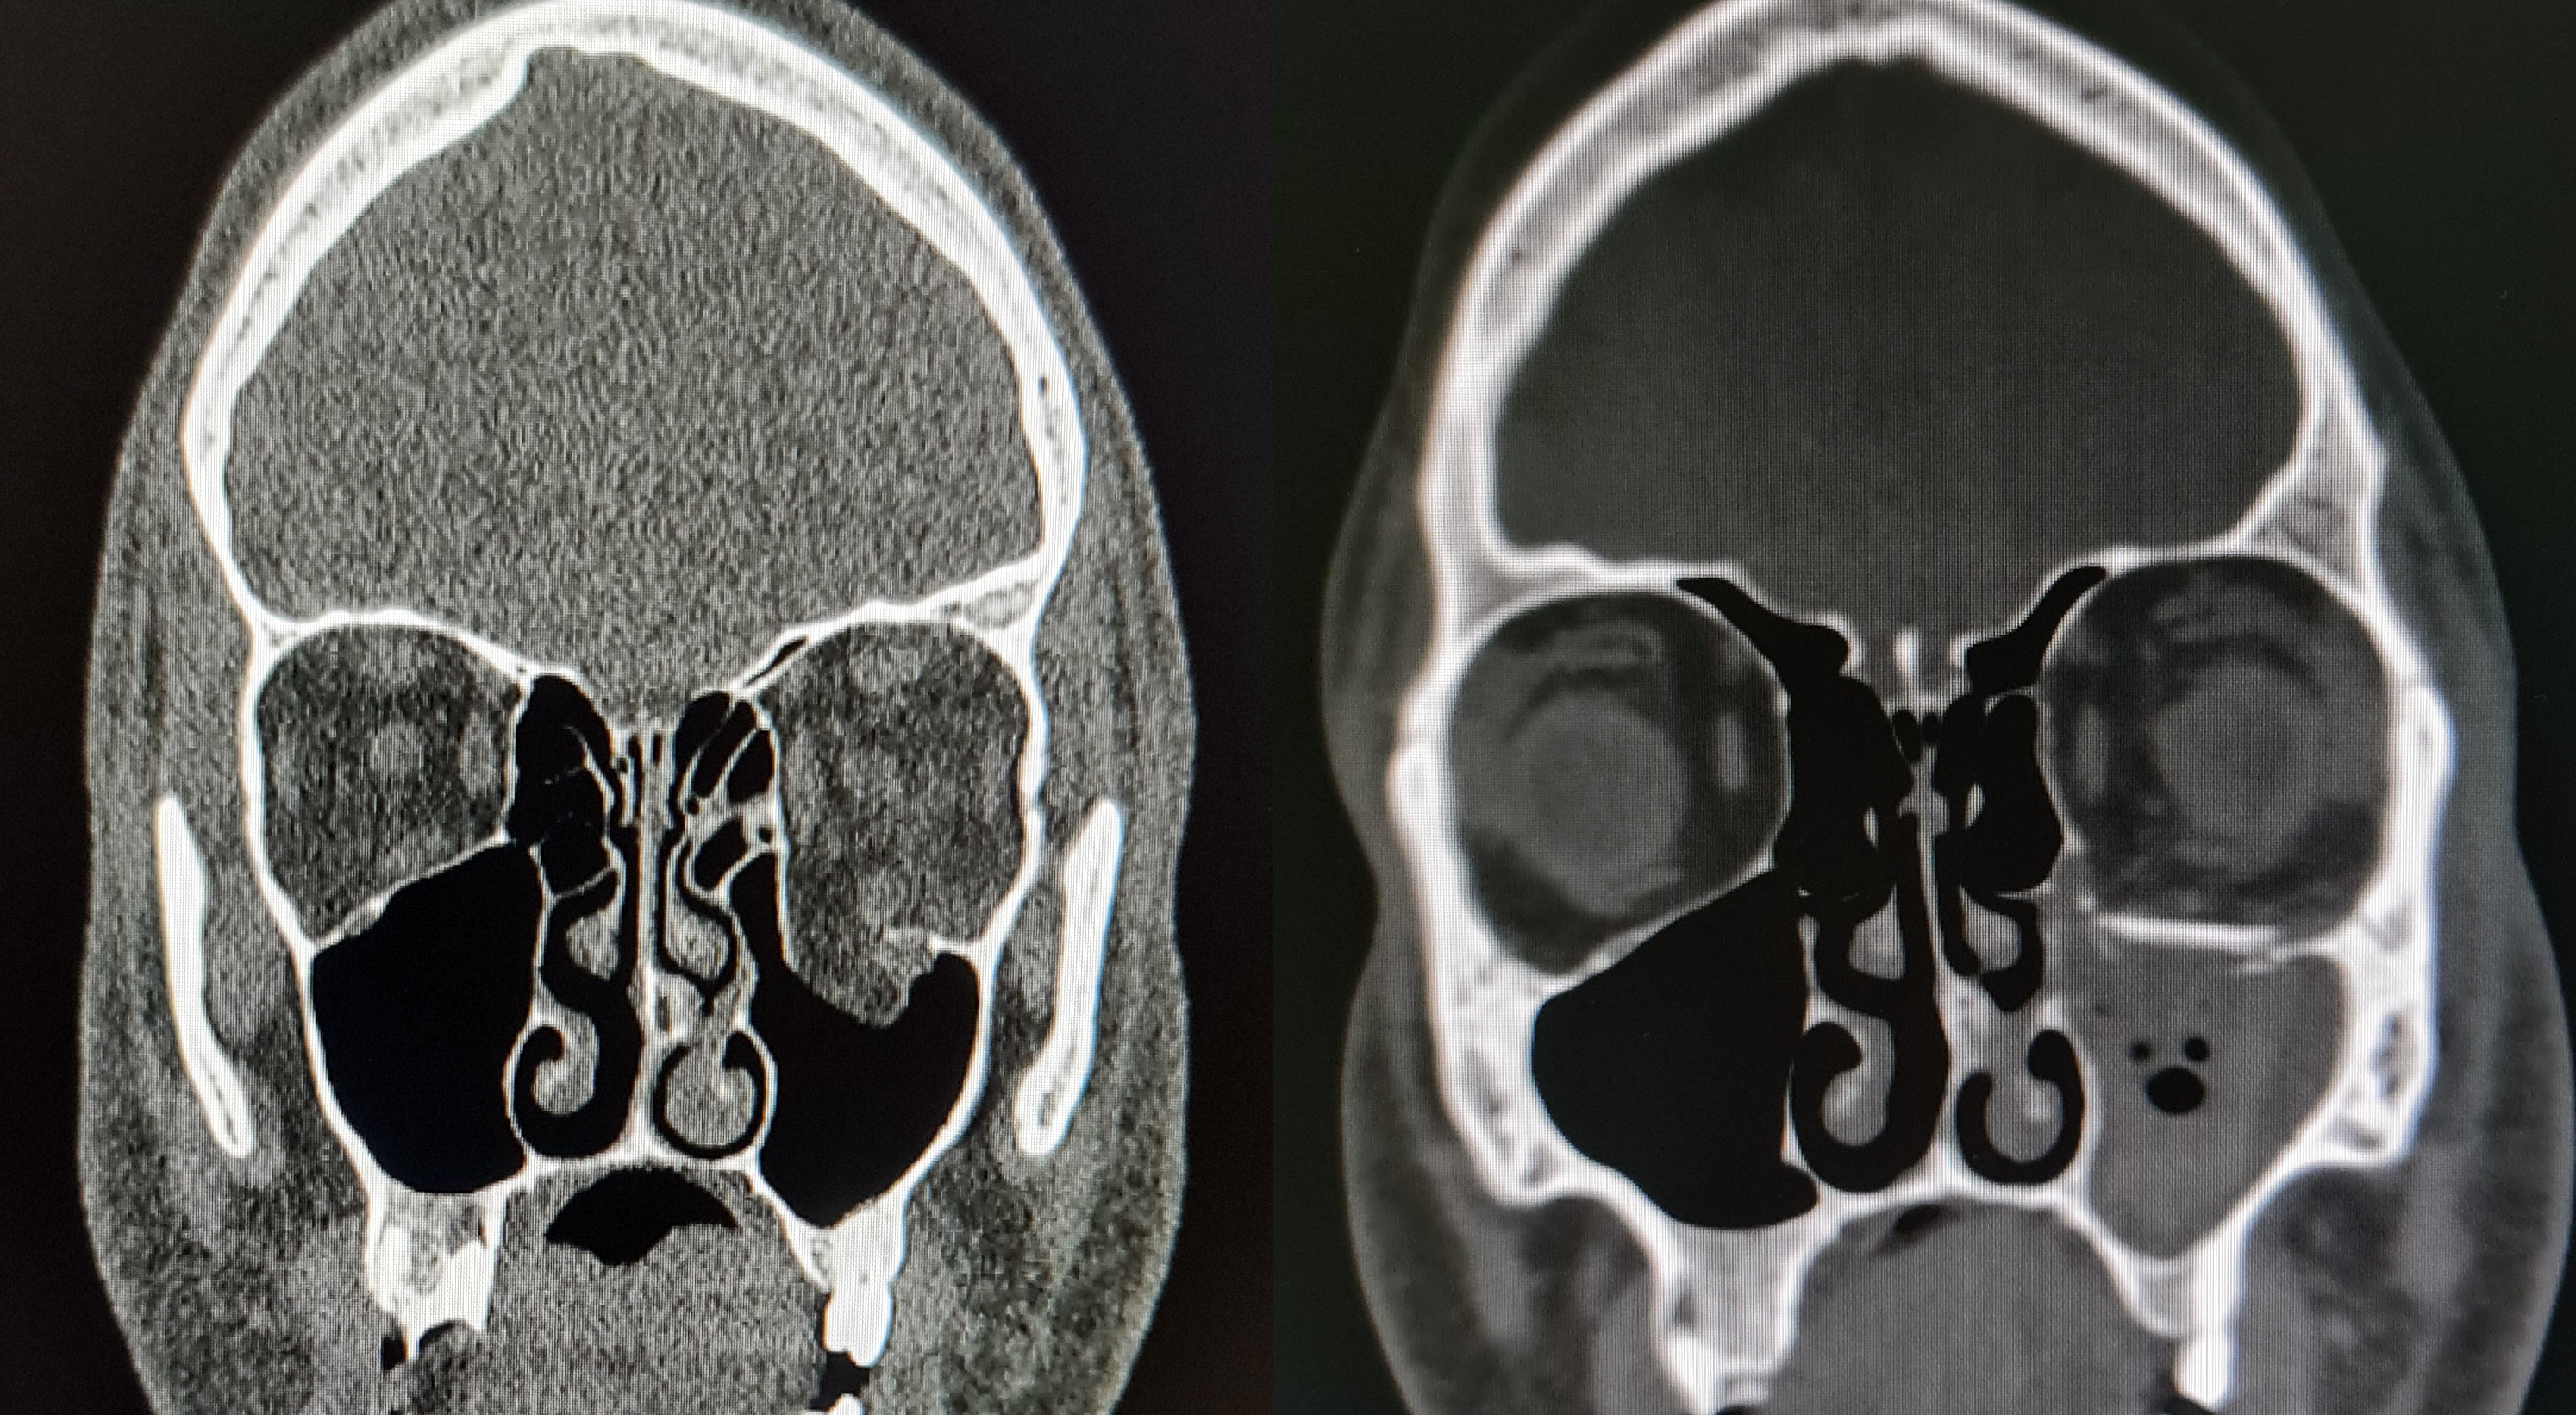

Orbita rekonstrüksiyonu - ameliyat öncesi ve sonrası BT

Detaylı muayene, 3D tomografi ve yüz analizi ile cerrahi planlama.